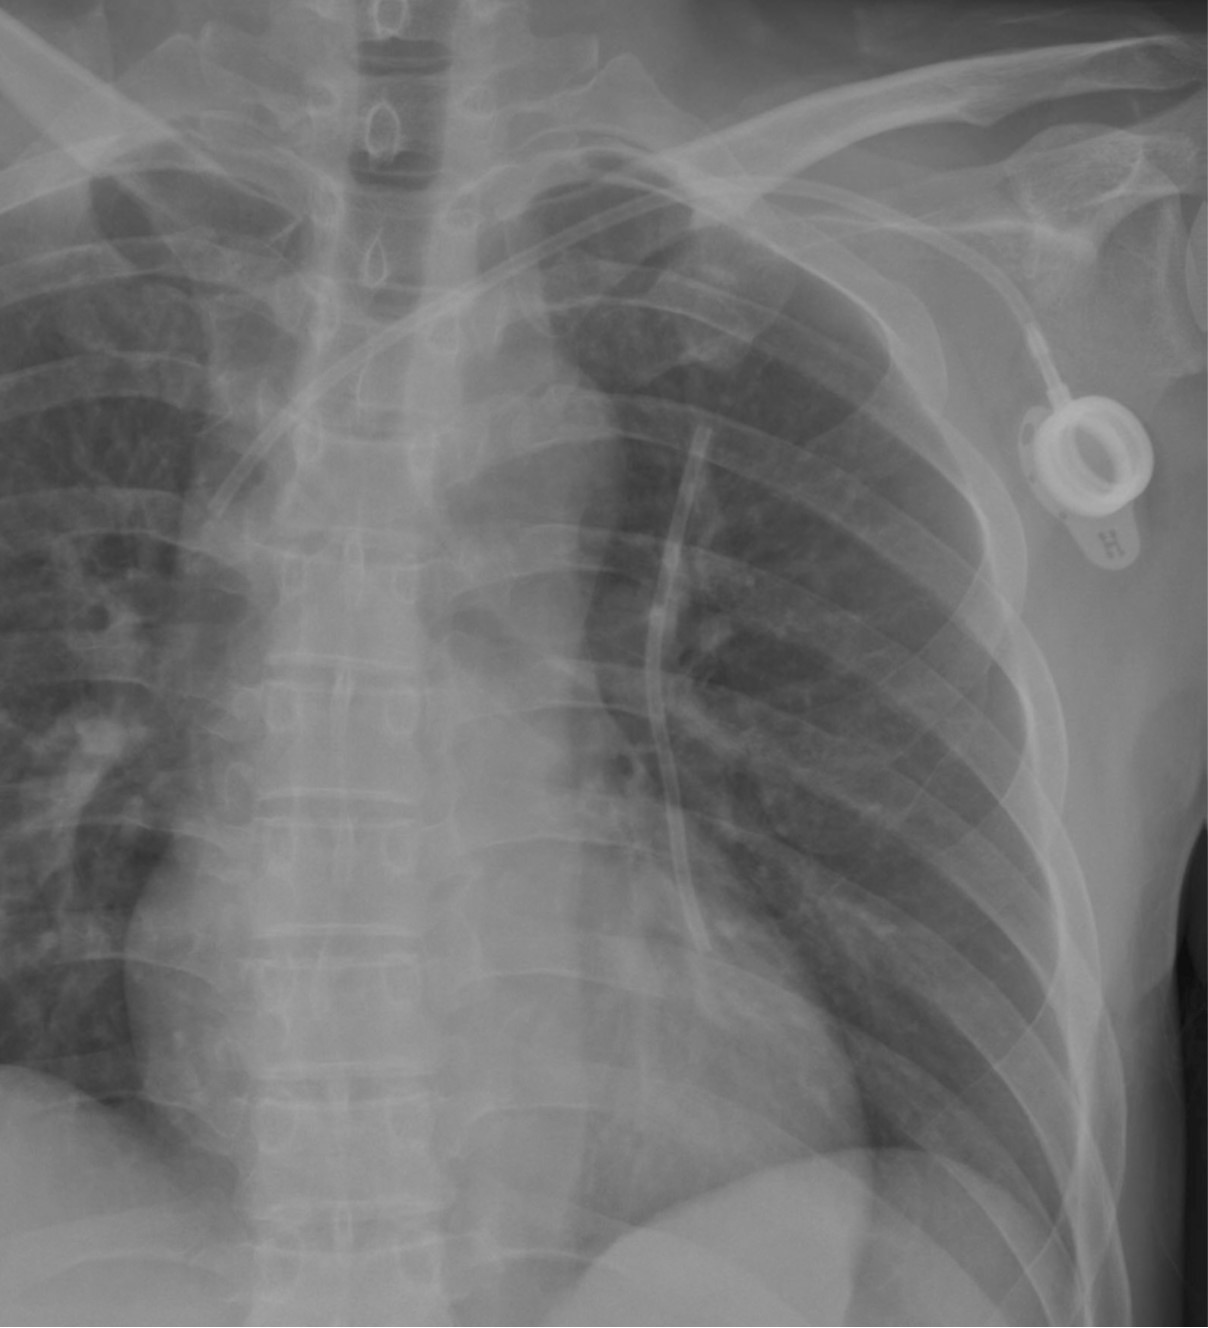

Fig. 2.

Fig. 2. A postero-anterior chest radiograph demonstrates fragmented chemoport catheter and another chemoport placed via the left subclavian vein.